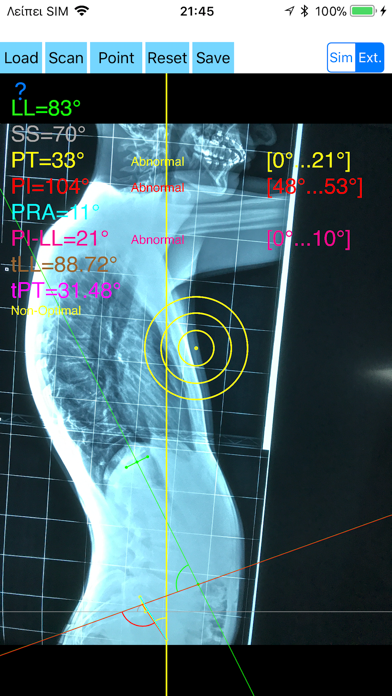

1. -By marking few points at the image of X-ray, the App calculates and offers a very convenient way to determine the most accurate possibly way at once, Pelvic incidence (PI), Sacral slope (SS), Pelvic Tilt (PT), Lumbar lordosis (LL), thoracic kyphosis, PI–LL Pelvic incidence Angle (PI) minus Lumbar lordosis Angle (LL) PI–LL, theoretical normal pelvic tilt (tPT),theoretical normal L1-S1 lumbar lordosis (tL1S1), Pelvic Radius Angle (PRA).

2. Radiographic parameters to evaluate objectively the spinopelvic sagittal balance are Pelvic incidence (PI), Sacral slope (SS), Pelvic Tilt (PT), Lumbar lordosis (LL).

3. -The app offers theoretical value estimation this is particularly useful because a sensible difference between theoretical value and measured value reveals a compensation phenomenon if the pelvis tilt (PT) is higher than its theoretical value, then it is due to pelvis retroversion, which is a compensation phenomenon.

4. Knowing the theoretical value of Pelvis Tilt (PT) provided it is easy to understand that a sensible difference between theoretical value and measured value is a compensation phenomenon.

5. Drawings in patients X-rays and precise measurements are important in order to quantify the magnitude of spinal deformities, to monitor the success or failure of treatment and thus optimise the management of patients according to the severity of the imbalance or even to identify patient at risk of degenerative spondylolisthesis or disk herniation.

8. The app offers a very convenient and accurate way to perform most common radiographic measurements for spine, at the spinopelvic juncture in a blink of an eye in front of your screen.

11. According to measured parameters the app categorises the severity of the imbalance of spine, in different stages: optimal or non optimal.